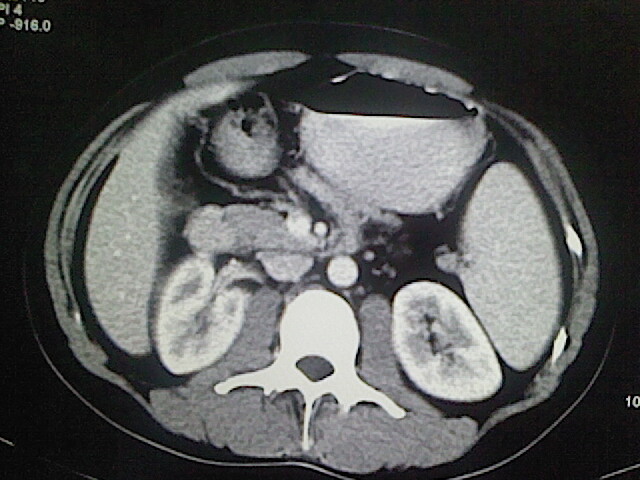

以下是引用卜一在2009-3-14 9:49:00的发言:[br]胆囊萎缩,胆囊壁不规则增厚,内部结构模糊,增强明显强化。另:肝左叶外侧段肝囊肿。支持:慢性胆囊炎!高度可疑:胆囊癌!

以下是引用余辉在2009-3-14 8:48:00的发言:[br]1)慢性胆囊炎。2)肝左叶外侧段肝囊肿。3)脂肪肝。[br]支持,胆囊萎缩,密度增高,不知b超具体有何提示,钙胆汁?结石?

以下是引用jiangjing在2009-3-14 10:18:00的发言:[br]1)慢性胆囊炎。2)肝左叶外侧段肝囊肿。3)脂肪肝。4.】建议行肝功能检查